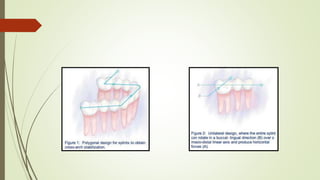

PRINCIPLES OF SPLINTING:

 The main objective of splinting is to decrease movement three-dimensionally.

 This objective often can be met with the proper placement of a cross-arch

splint.

 Conversely, unilateral splints that do not cross the midline tend to permit the

affected teeth to rotate in a faciolingual direction about a mesio-distal linear

axis.